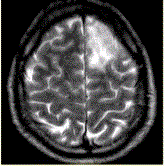

问题 患者男,37岁。癫痫发作数次。MRI显示如下图。 关于MRI表现的描述正确的是

选项 A.左侧额叶肿块,边界清晰 B.左侧额叶肿块,边界不清 C.病变邻近脑沟消失,同时累及灰白质 D.病变无明显强化 E.病变累及灰质,皮层下白质正常 F.病变呈楔形

答案 BCDF